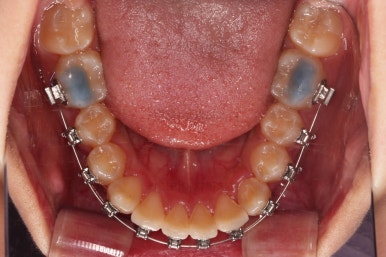

장치를 부착했어요.

윗니는 상대적으로 많이 보이기 때문에 세라믹, 아랫니는 많이 보이지 않기 때문에 메탈로 부착했어요.

동래교정치과 장치를 부착한 직후의 모습입니다.

입은 약간 더 튀어나오는 편이었고 상대적으로 많이 보이는 윗니를 세라믹으로 해서 아랫니는 메탈이라 하더라도 심미적으로 크게 손해는 아니었어요.